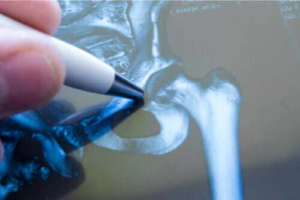

Efter ett allvarligt fall är akut medicinsk vård avgörande, särskilt om patienten är äldre. Läkaren kommer att utföra en akut röntgenundersökning, som visar omfattningen av frakturen.